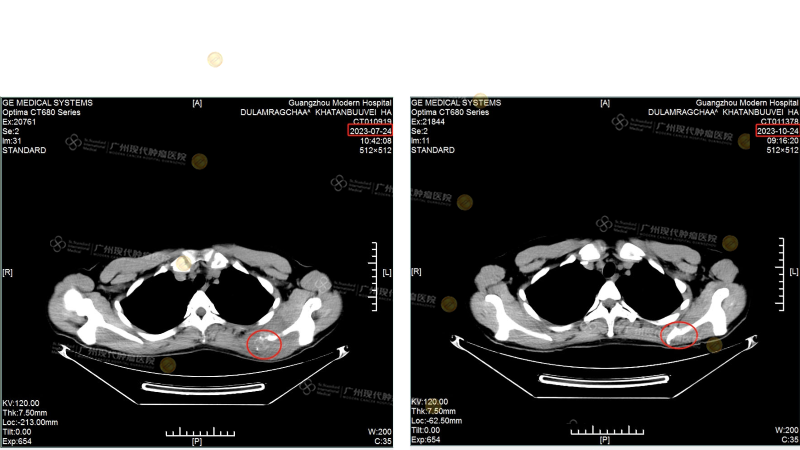

[ภาพด้านซ้ายคือ CT scan ของกระดูกสะบักในเดือนกรกฎาคม: ขนาดของก้อนเนื้อประมาณ 46 มม.×79 มม. และลุกลามเข้าไปในกระดูกสะบัก]กับ[ภาพด้านขวาคือ CT scan ของกระดูกสะบักในเดือนตุลาคม ก้อนเนื้อหายไป]

[ภาพด้านซ้ายคือ CT scan ของต่อมน้ำเหลืองที่คอในเดือนกรกฎาคม: ก้อนเนื้อมีเส้นผ่านศูนย์กลางประมาณ 50 มม.]กับ[ภาพขวา CT ต่อมน้ำเหลืองที่คอในเดือนตุลาคม ก้อนเนื้อหายไป]